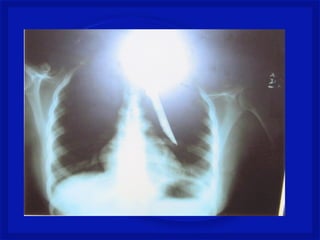

•Perfuração da coluna (arma branca, tiro

ou estilhaço de bomba na coluna)

•Lesão medular completa ou incompleta,

associada ou não a lesão dos nervos

espinhais e/ou tronco dos plexos

nervosos.

•Quadro neurológico é variável.

Mecanismo de Trauma Raqui-

Medular Penetrante